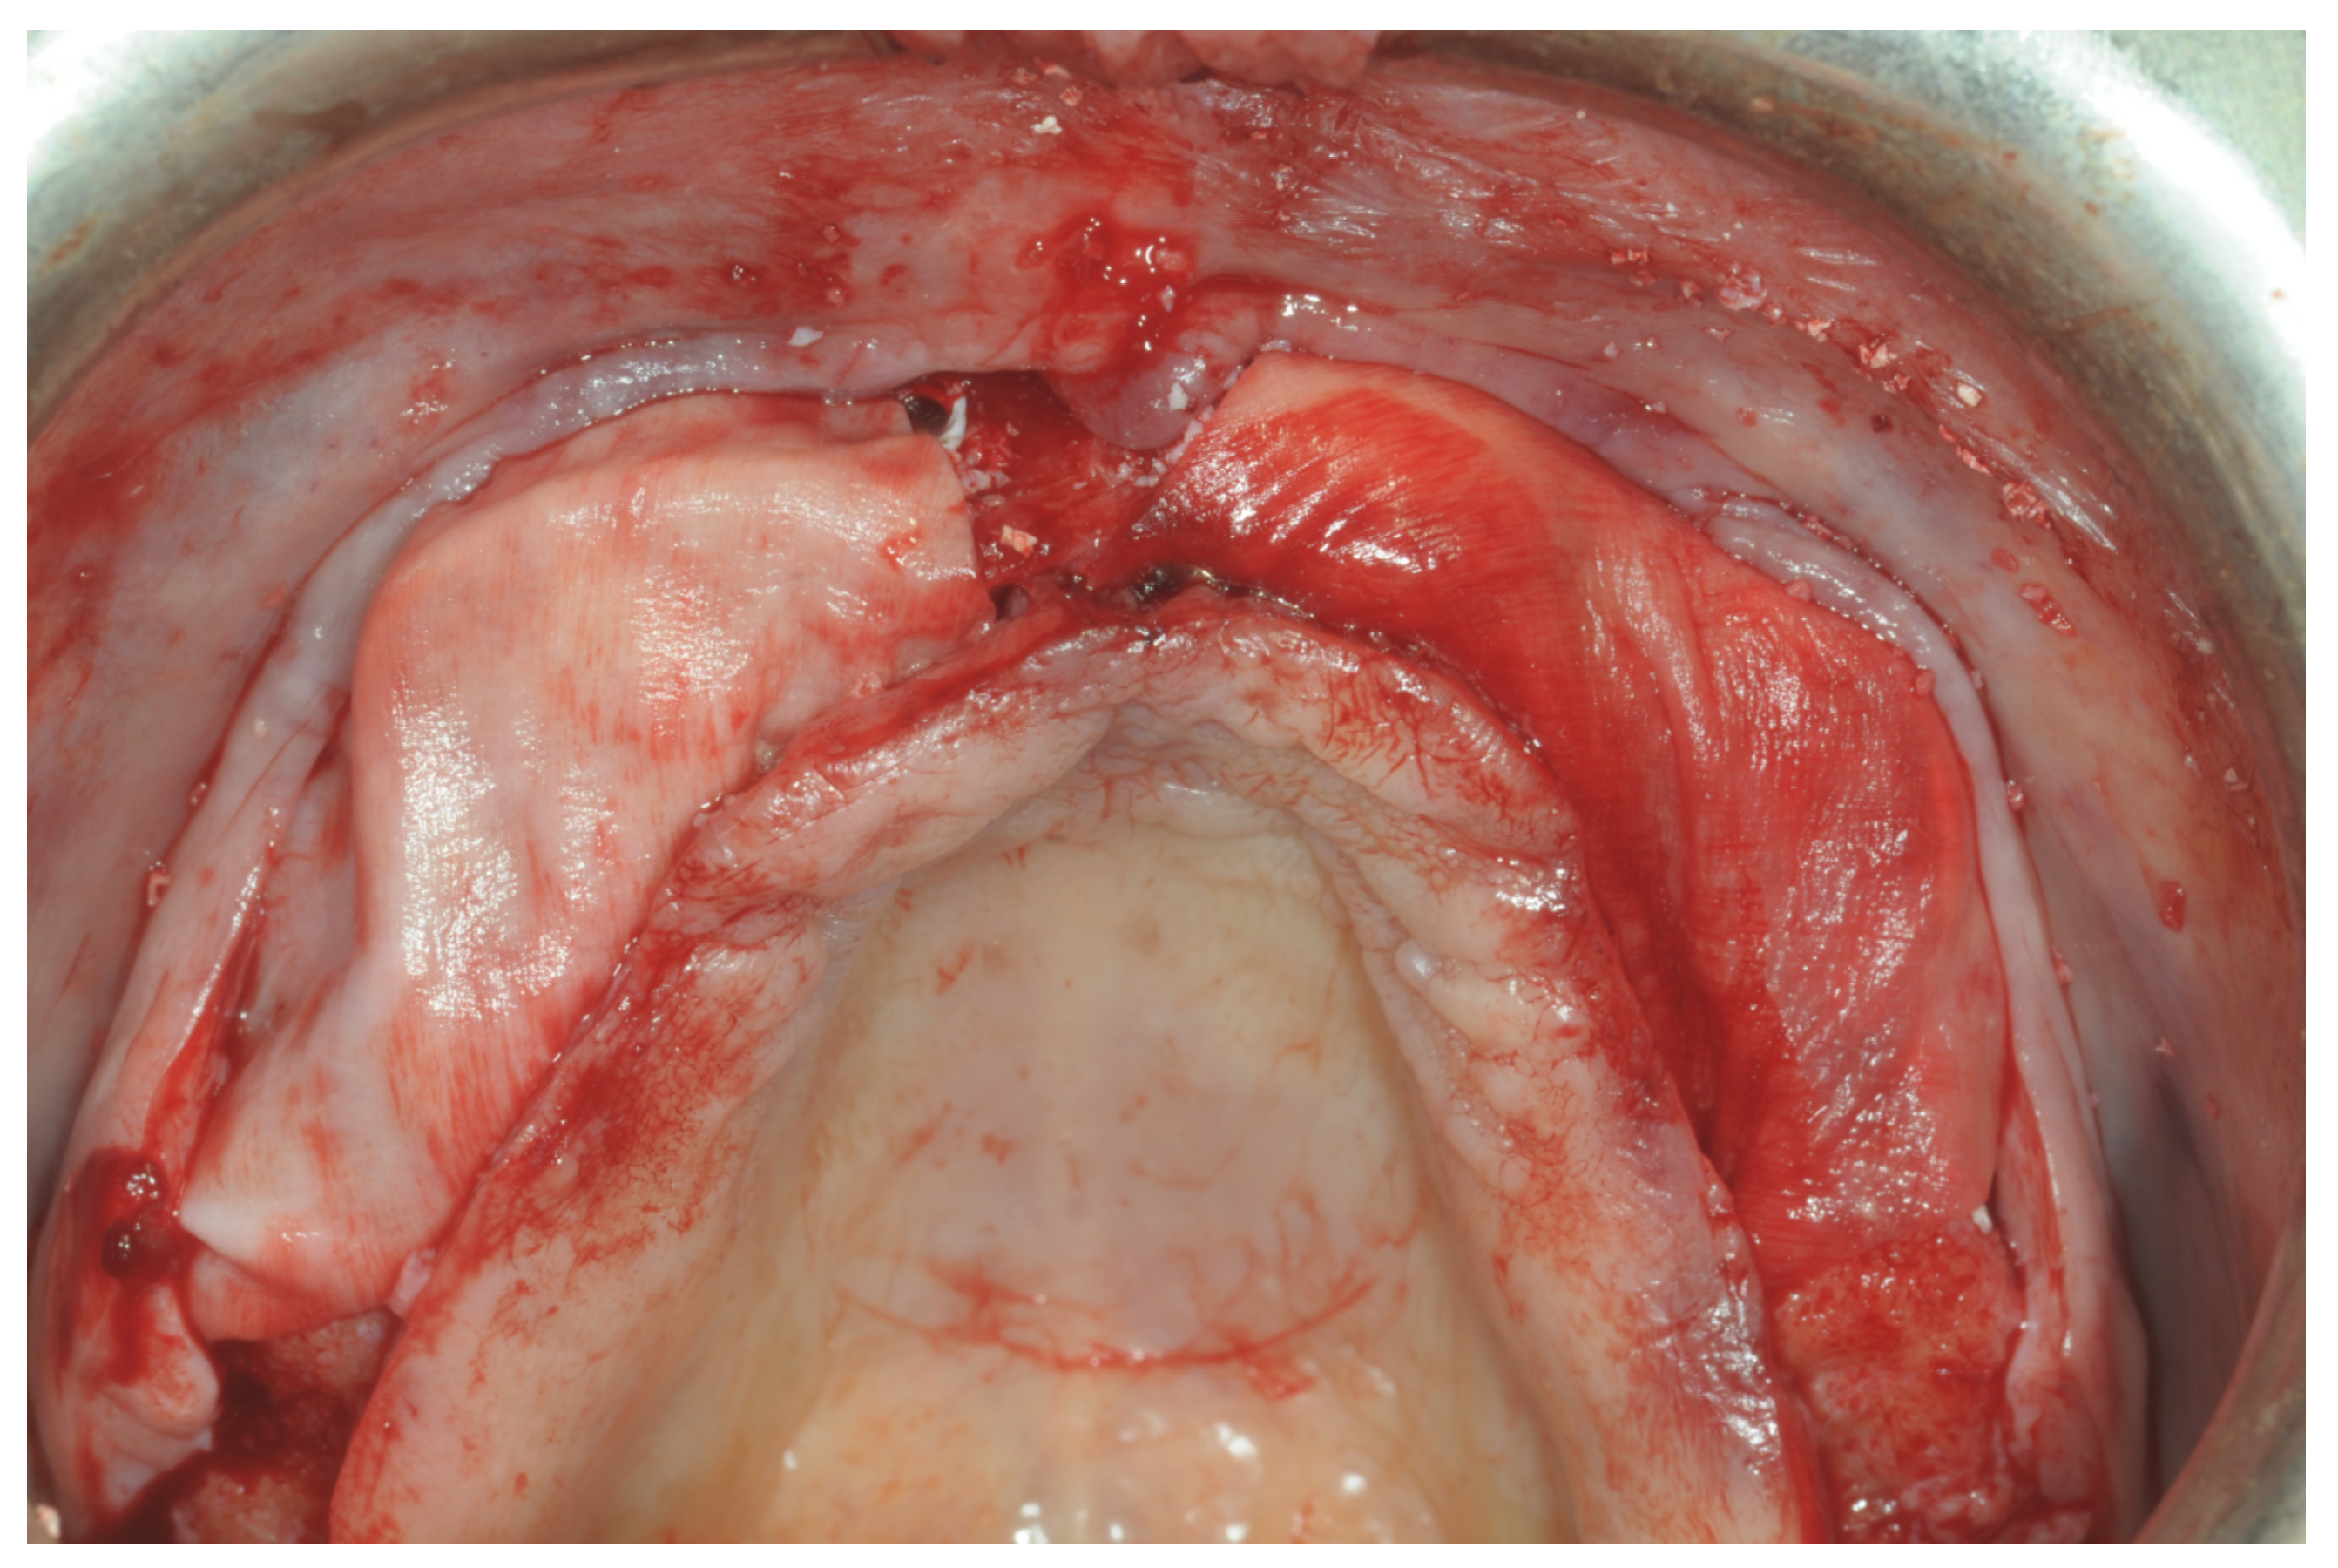

Figure 6. Surgical exposure of the augmented area 9 months after GBR.

At this point, a non-resorbable high-density PTFE barrier (Cytoplast TXT-200, Osteogenics Biomedical, Lubbock, TX, USA) was designed on the basis of the bone defect shape and was distally blocked on the bone by two titanium pins (Kalos, Nike, Orbetello, Italy). A mixture of 50% autogenous bone harvested from the mandibular ramus with the use of a scraper and 50% inorganic bovine bone (Bio-Oss, Geistlich, Wolhusen, Switzerland) was placed in the recipient site and the membrane was pulled and blocked on the bone with two mesial pins. With this particular, and innovative, non-resorbable membrane management, the graft was compressed and fixed on the recipient bed (Figure 9, Figure 10 and Figure 11). The occlusal portion of the graft was then covered with a layer of a collagen resorbable barrier (Bio-Gide, Geistlich) (Figure 12) and peri-osteal incisions were performed to make the flap passive.